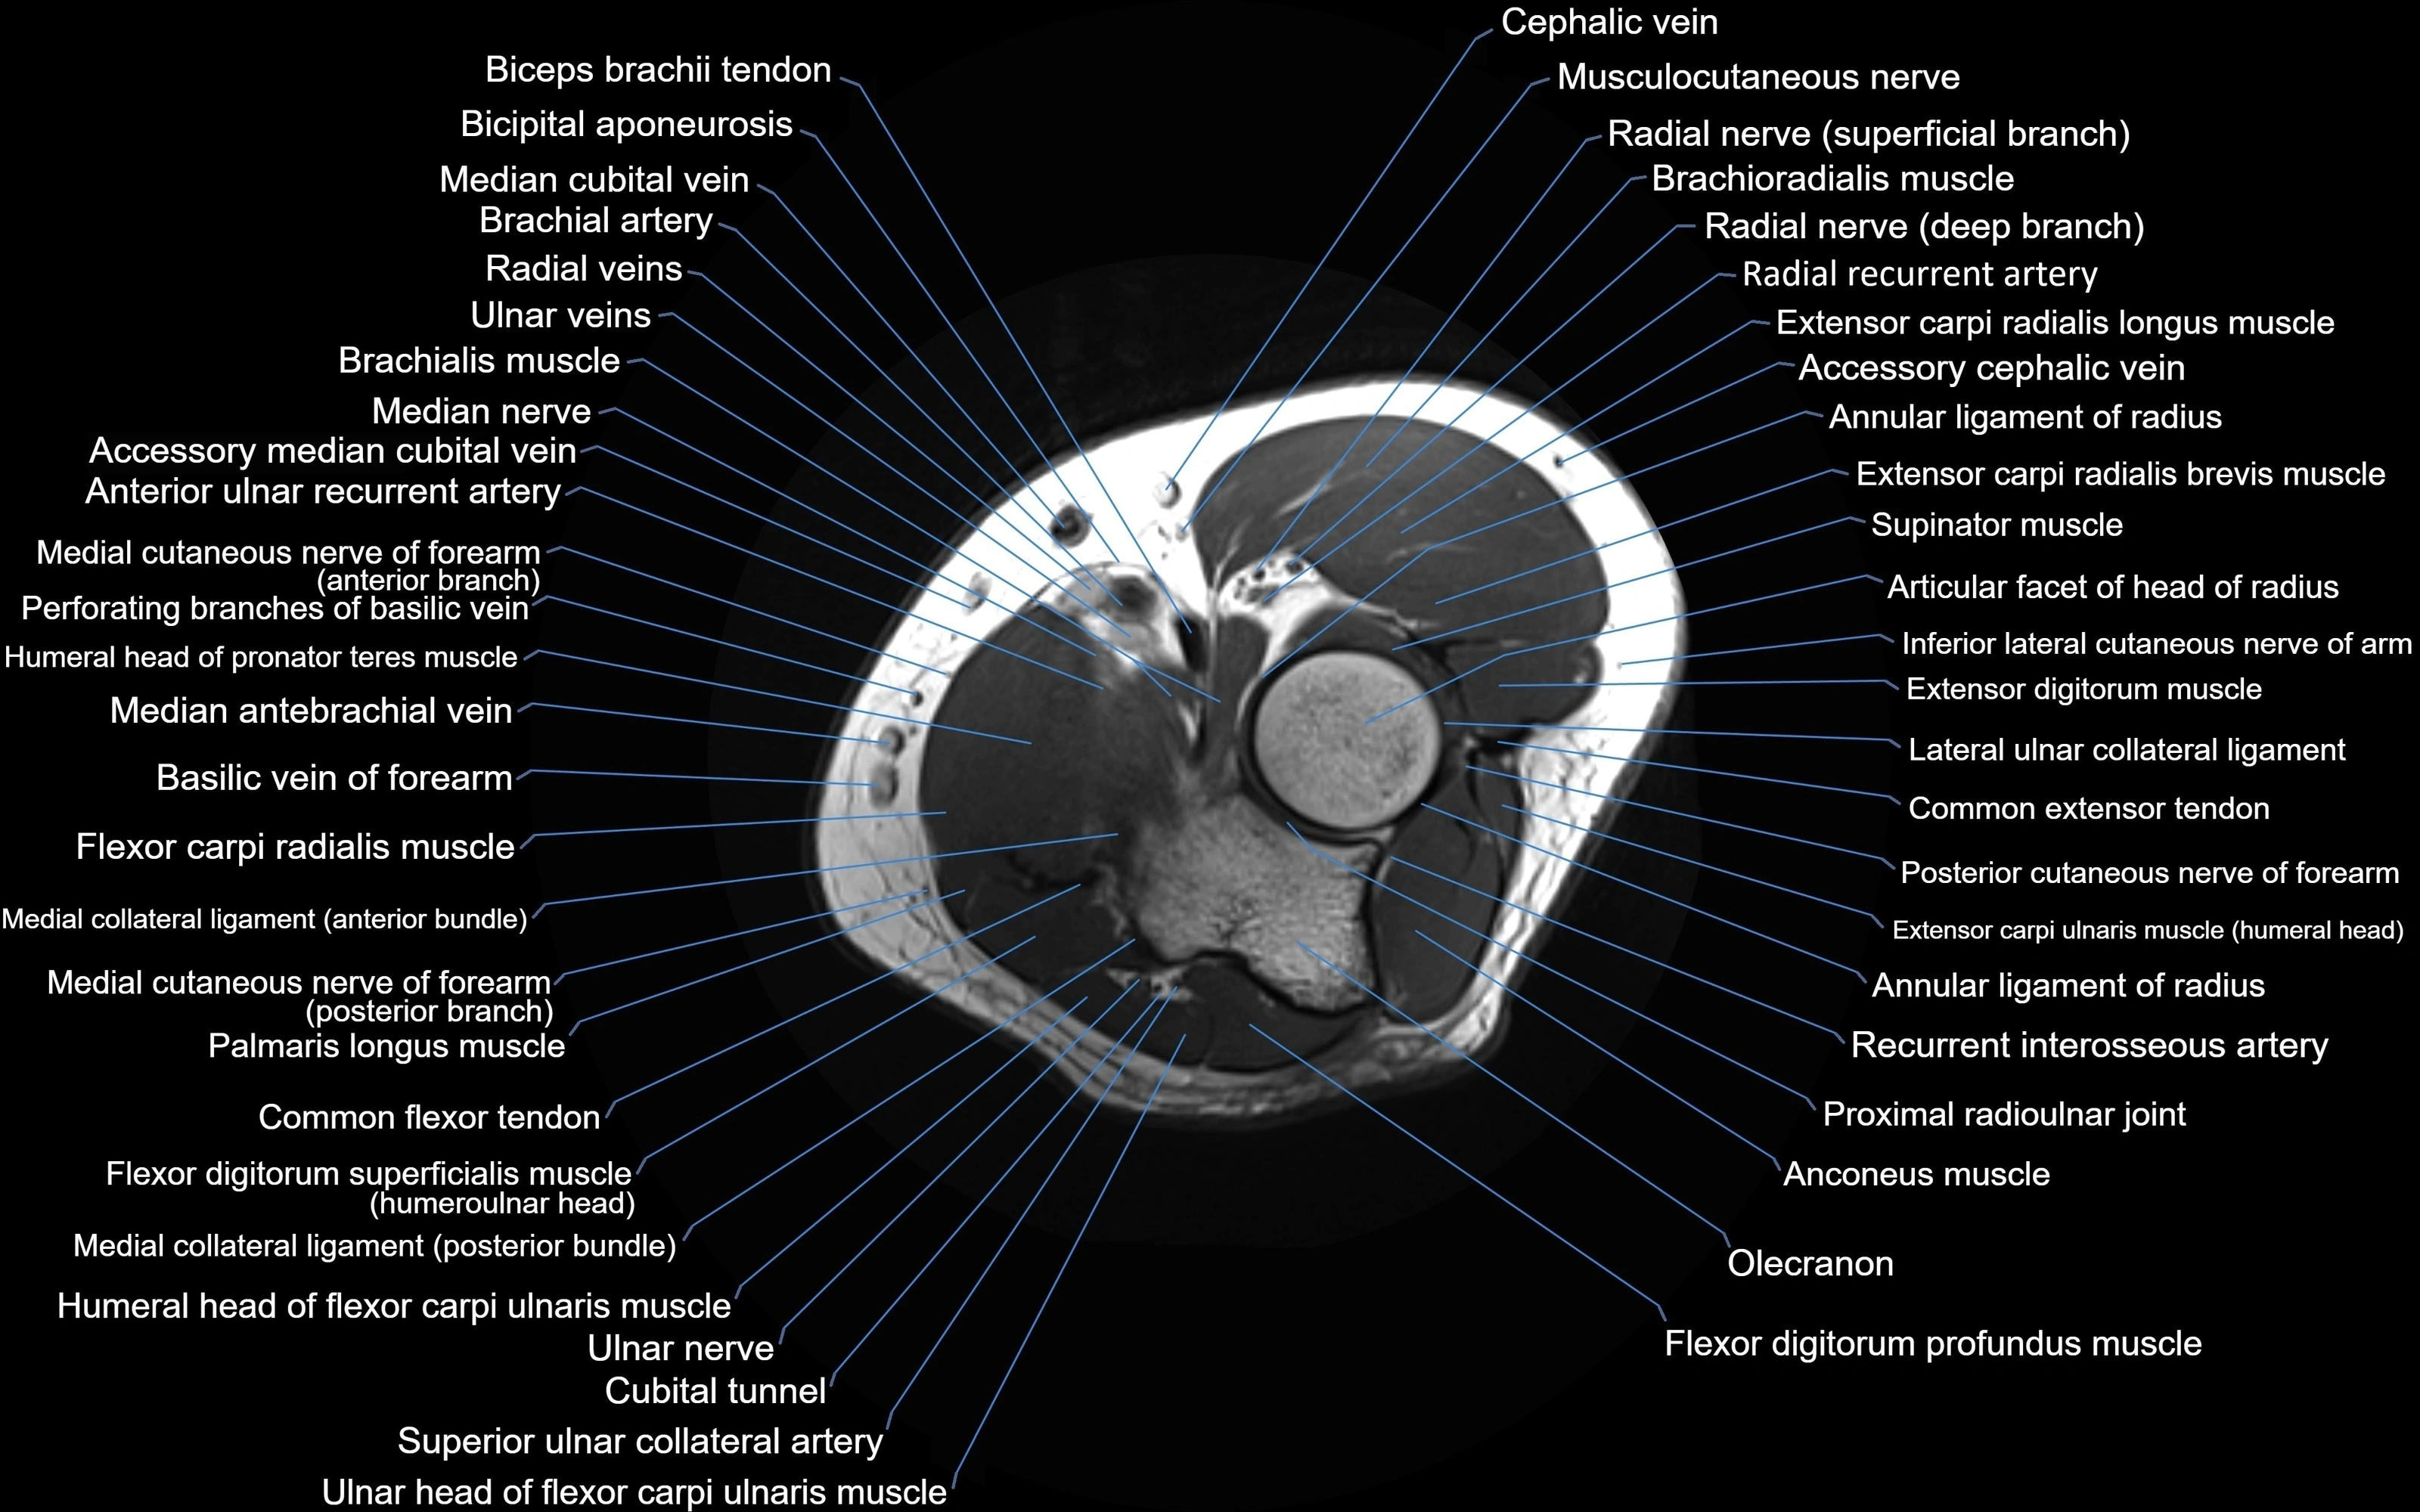

MRI image

image